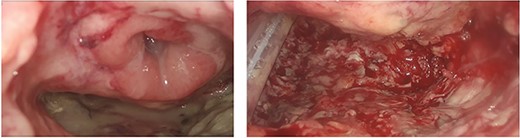

A 75-year-old Caucasian man was referred to our department on May 2022 because of a positive fecal occult blood test; subsequent colonoscopy showed an endoluminal substenosing lesion, located at sigmoid-rectal junction and extended distally for 5 cm. The tumoral bulk appeared centrally ulcerated and occupied more than three-fourth of the rectal circumference. The panel of biopsies resulted positive for well-differentiated adenocarcinoma. An angio-CT scan confirmed the presence of a sigmoid-rectal wall thickening, extended distally for about 6 cm, with significative narrowing of colonic lumen. Lateral spread appeared limited to the muscolaris propria, whereas the mesorectal component was unaffected; the presence of T2 lesion at preoperative diagnostic work-up was confirmed by MRI while neither hepatic nor pulmonary metastasis were detected. Tumor markers were within normal range. At physical examination, the patient appeared overweight (BMI 30.5), with no other significative comorbidity. Pre-operative staging led the Multidisciplinary Tumor Board to authorise a surgical approach. The patient underwent laparoscopic low anterior rectal resection with total mesorectal excision, with transanal end-to-end stapled colorectal anastomosis (7 cm from the anal verge) and ileostomy. Histological report of resected specimen confirmed the diagnosis of a G2 rectal adenocarcinoma, staged as pT3 pN1a R0, whereas the quality of mesorectal excision was graded as 3 (complete mesorectal fascia) according to Quirke classification. On the fifth post-operative day, the patient developed an increase in body temperature (37.8°C), in WBC count (10 × 103/uL) and in CRP plasmatic levels (6.63 mg/dL), as well as a corpuscular discharge from perianastomotic drainage; at physical examination, the patient showed a moderate tenderness on lower left abdomen with no clear signs of peritonitis. Early abdominal angio-CT scan showed a 15-mm discontinuity on the posterior wall of colorectal anastomosis, with perirectal fluid and extraluminal gas collection (Fig. 1). Low-flow endoscopic exploration confirmed the anastomotic wall defect in the right postero-lateral side, connected to a cavity filled with necrotic tissue (Fig. 2). Given the presence of ileostomy and perianastomotic surgical drainage and the absence of peritonitis signs with proper control of patient’s hemodinamics, we opted for a non-surgical treatment. On the sixth post-operative day, the patient underwent an Endo-SPONGE® device placement into the AL cavity, performed with TAMIS approach [7]. With the patient in lithotomy position, a GelPOINT® path transanal access platform was positioned; laparoscopic insufflation pressure was set at 10 mmHg. The right posterolateral anastomotic wall defect was visualised (Fig. 3), then the AL cavity was carefully measured (3 cm × 4 cm), washed with saline solution and explored up to the tip of surgical drainage. The polyurethane sponge was positioned under laparoscopic vision and then connected to the vacuum suction system, set at −40 mmHg. The Endo-SPONGE® device was replaced every 72 h for 2 weeks, then every 96 h for another 10 days; size and shape of the device were modified and gradually reduced according to the decreasing size of the cavity. Control CT scan and rectosigmoidoscopy confirmed the almost complete obliteration of the AL cavity. The Endo-SPONGE® device and the abdominal drainage were removed on the 25th post-operative day and the patient was then discharged without further complications. The patient has been addressed to adjuvant treatment protocol; a 3-month control CT scan showed neither distant metastases nor residual perirectal cavity. Once adjuvant treatment is completed, patient will be enrolled for colorectal anastomotic check and closure of ileostomy.

Contrast CT scan: ‘Abundant fluid-air presence in the presacral space and in the mesorectum at the level of the colo-rectal anastomosis, and a discontinuity on the posterior side of the colonic wall’.